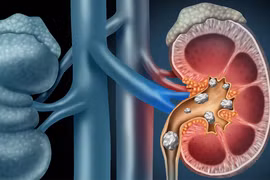

Bệnh sỏi thận có diễn biến âm thầm, người mắc bệnh sỏi thận có thể không nhận ra cho tới khi đi khám. Nếu không được phát hiện và điều trị kịp thời thì rất có thể sẽ dẫn tới biến chứng suy thận.